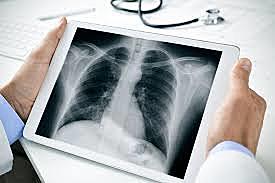

-Wilhem Rontgen halló los rayos-x (noviembre 8, 1895)

-Wilhem Rontgen obtuvo la imagen de la mano de su esposa. (noviembre 14, 1895)

-Wilhem Rontgen publico sobre una nueva clase de rayos. Después de su descubrimiento se empezaron a usar para diagnostico medico.

descubridor de la fluoroscopia fue Wilhelm Roentgen

-Enero 3. Alemania se publico el descubrimiento de los rayos X dando a demostrar sus posibles usos en la medicina

-Enero 11. Rayos X usados en una cirugía

El desarrollo del intensificador de imagen de rayos X y la cámara de televisión (fluoroscopia)

-La tomografía computada (TC) fue creada y desarrollada por sir Godfrey Hounsfield

Surge la tomografía computada helicoidal, la cual tenía ventajas considerables a su antecesora la Tomografía Axial Computada (TAC).

• Rayos X Digital

Rayos X Digital

Creación de la maquina rayos-x digital